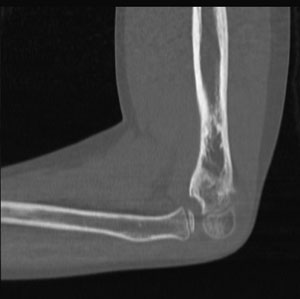

Grayscale medical CT image of a human elbow joint showing the humerus, radius, and ulna bones in cross-section.The scientific unit of measurement for radiation dose is the Gray (Gy), which is a measure of the amount of X-ray energy absorbed per unit mass. Other radiation units include rad, rem, roentgen, and Sievert.